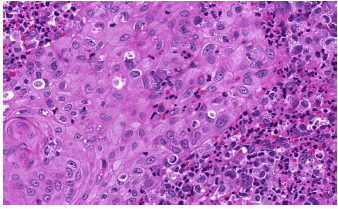

Homem, 39 anos, com relato de lesões placas violáceas nos membros inferiores. Assinale a alternativa que apresenta o diagnóstico que a figura abaixo ilustra.